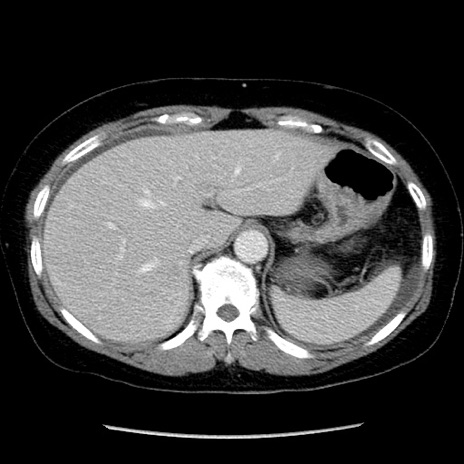

矢状断像